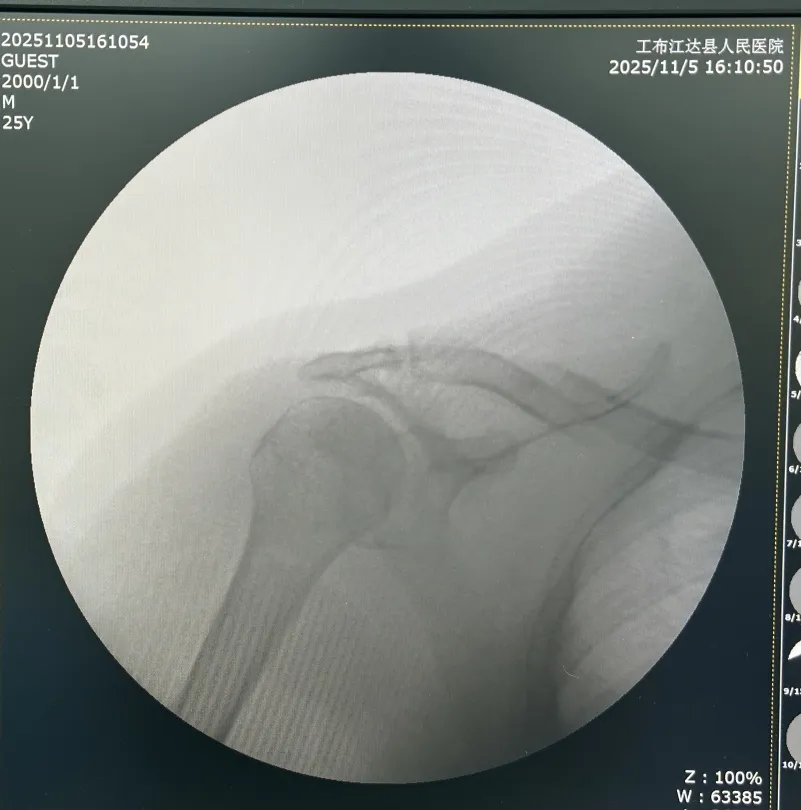

▪ 精准复位固定技术:针对患者右锁骨骨折,实施切开复位内固定术。新院区新增的C臂机提供实时精准影像支持,李伟濂医师凭借丰富临床经验,完成骨折端精准对位与内固定操作,这也是当地首次独立开展此类标准化骨科手术。